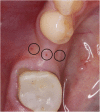

Methods: After randomization, 31 fully threaded titanium implants were inserted in 31 patients (16 men and 15 women) in the lower mandible using a split-flap technique. In the test group (10 patients), mucosa was treated with a PRF membrane. In the control group (21 patients), implantation was realized without soft tissue augmentation. Tissue thickness was measured at point of implant insertion (baseline) and at time of reentry after 3 months. Standardized digital radiographs were obtained for evaluation at time of implant placement, reentry after 3 months and at a 6-month follow-up. Data was analyzed by an independent examiner.